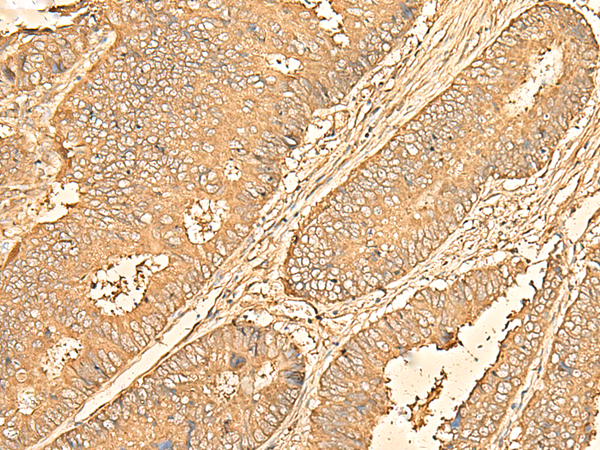

IHC positive control:

Human cervical cancer and Human colorectal cancer